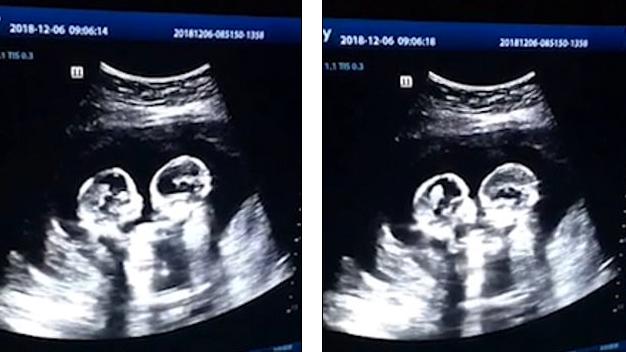

O mamă din China a avut parte de surpriza vieții ei când a mers la o ecografie. Femeia a văzut de față cu medicul cum cele două fetițe parcă se iau la bătaie, chiar în burta ei. Tatăl micuțelor a filmat întregul moment, surprins chiar și el de ce poate vedea. Bărbatul a spus amuzat că nu se aștepta ca fiicele lui să apară pe internet chiar înainte de a se naște. Gemenele au primit chiar și porecle: Cireașă și Căpșună, după fructele preferate ale mamei. Imaginile au strâns 2.5 milioane de like-uri și peste 80 mii de comentarii.